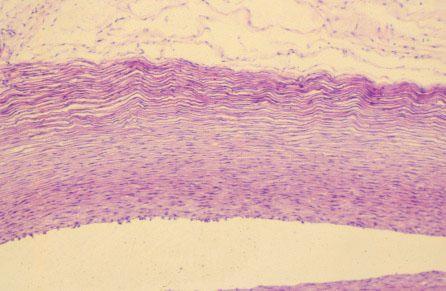

XI-60 (5) Slide 105, Umbilical Cord (H&E). Medium power view of the umbilical vein. Note the thick tunica media. Endothelial cells (simple squamous cells) are also visible.